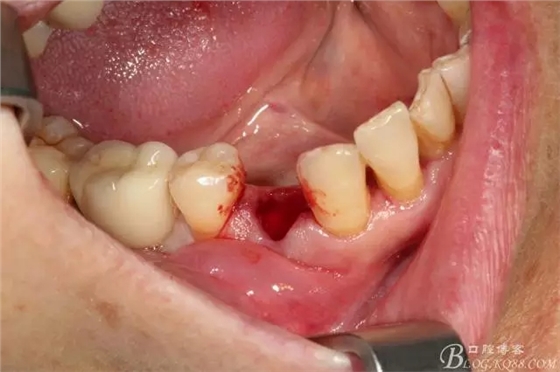

簡(jiǎn)單備洞以后植入種植體 植體和頰側(cè)空間距離大于2毫米 注意沒有植骨

這個(gè)角度更能看到植體與頰側(cè)骨壁的空間了

適當(dāng)塞入膠原塞 簡(jiǎn)單縫合